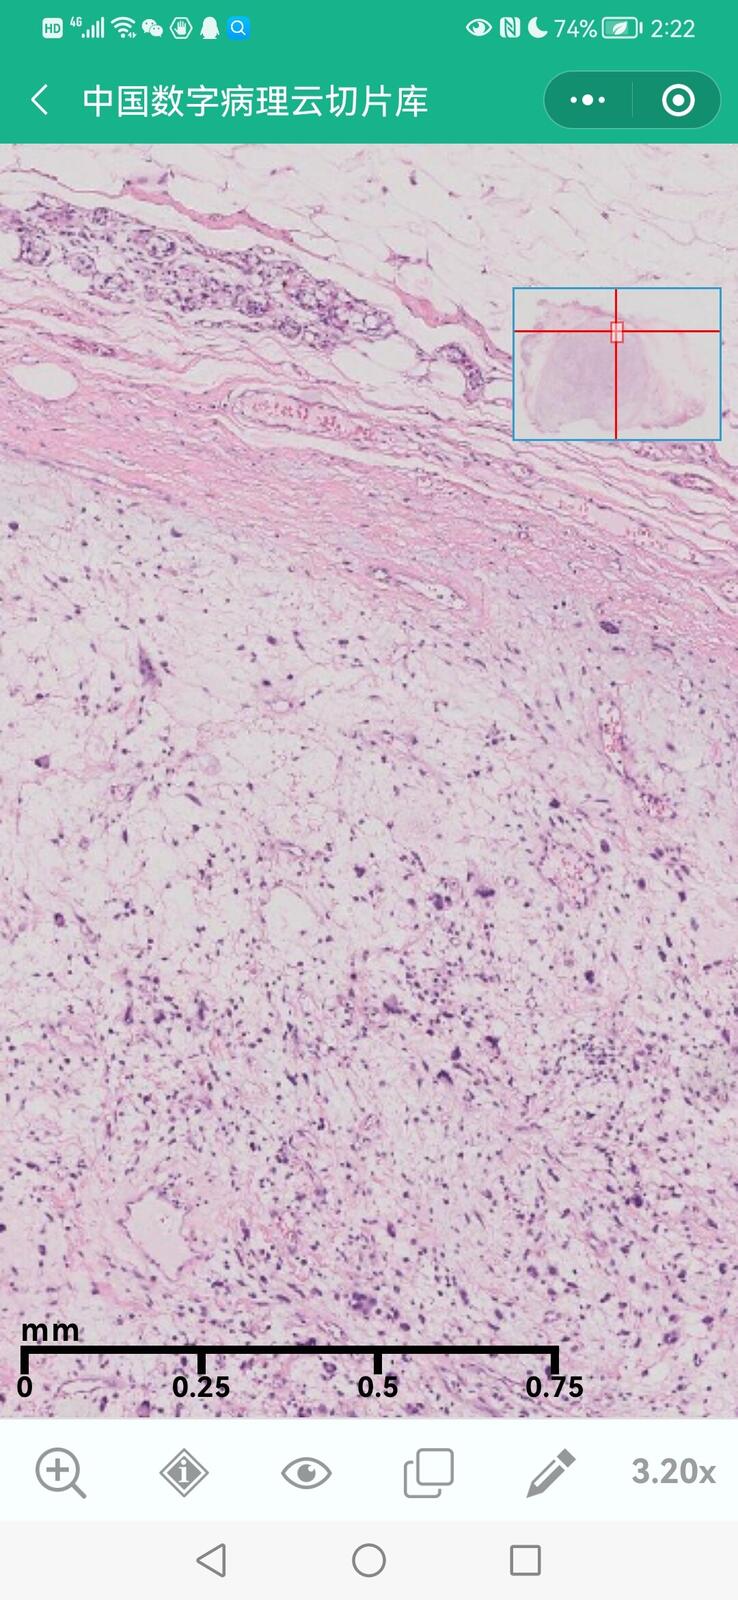

乳腺多形性脂肪肉瘤